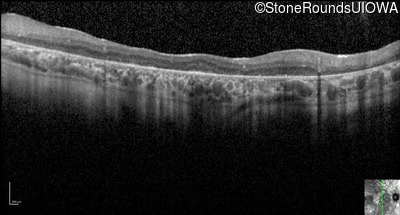

Optical Coherence Tomography - Right - 20/200 +2

Exemplar / OCT Stack